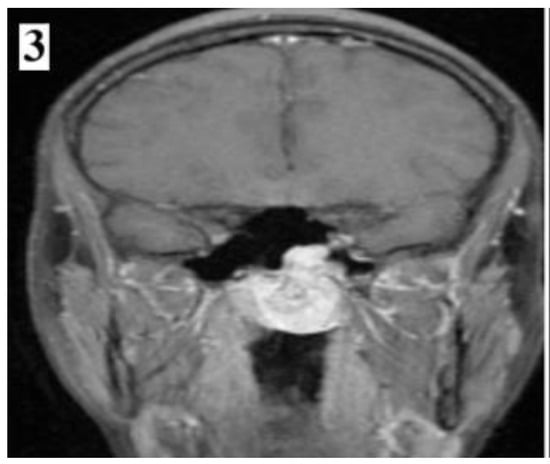

Figure 7.

Preoperative MRI of a stage IIC juvenile angiofibroma. The Holman-Miller sign (the anterior bowing of the posterior maxillary wall) on the CT scan (part 1).